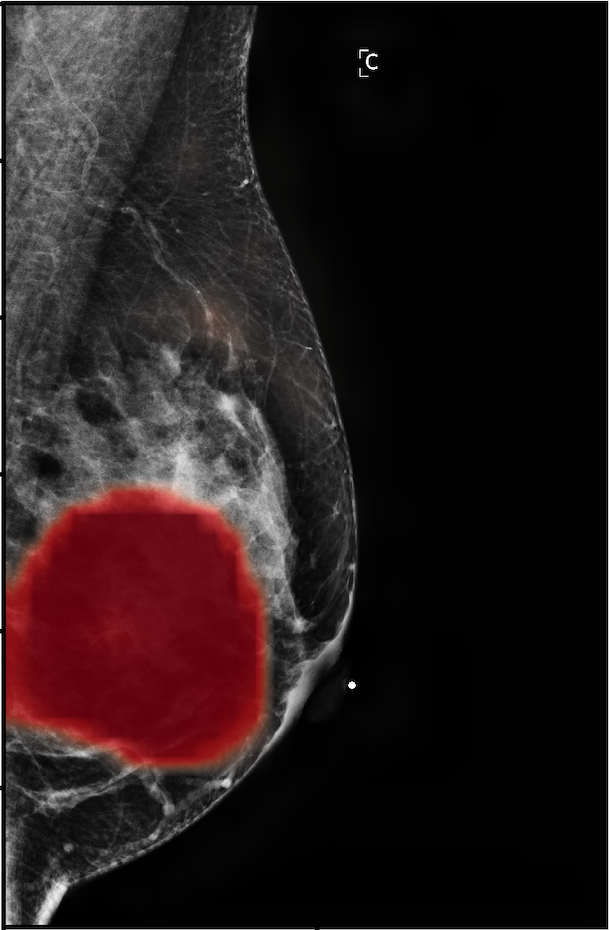

In Figure 7, we visualize saliency maps for four samples selected from the test set. In the first two examples, the saliency maps are highly activated on the annotated lesions, suggesting that our model is able to detect suspicious lesions without pixel-level supervision. Moreover, the attention is highly concentrated on ROI patches that overlap with the annotated lesions. In the third example, the saliency map for benign findings identifies three abnormalities. Although only the top abnormality was escalated for biopsy and hence annotated by radiologists, the radiologist’s report confirms that the two non-biopsied findings have a high probability of benignity and a low probability of malignancy. In the fourth example, we illustrate a case when there is some level of disagreement between our model and the annotation in the dataset. The malignancy saliency map only highlights part of a large malignant lesion with segmental coarse heterogeneous calcifications. This behavior is related to the design of : a fixed pooling threshold cannot be optimal for all sizes of ROI. The impact of is further studied in 3.6. This example also illustrates that while human experts are asked to annotate the entire lesion, CNNs tend to emphasize only the most informative regions. While no benign lesion is present, the benign saliency map still highlights regions similar to that in the malignancy saliency map, but with a lower probability than the malignancy saliency map. In fact, calcifications with this morphology and distribution can also result from benign pathophysiology [42].

In addition, we observe that GMIC is able to provide meaningful localization when the lesions are hardly visible to radiologists in the image. In Figure 8, we illustrate a mammographically occult mammogram of a 59-year old patient with no family history of breast cancer and dense breasts. There is an asymmetry in the left lateral breast posterior depth which appears stable compared to prior mammograms and was determined to be benign by the reading radiologist. However, the saliency map of malignant findings successfully identifies the malignant lesion on the screening mammogram. Same day screening ultrasound (sagittal image) demonstrated a 1.2 cm irregular mass; ultrasound biopsy yielded moderate grade invasive ductal carcinoma.